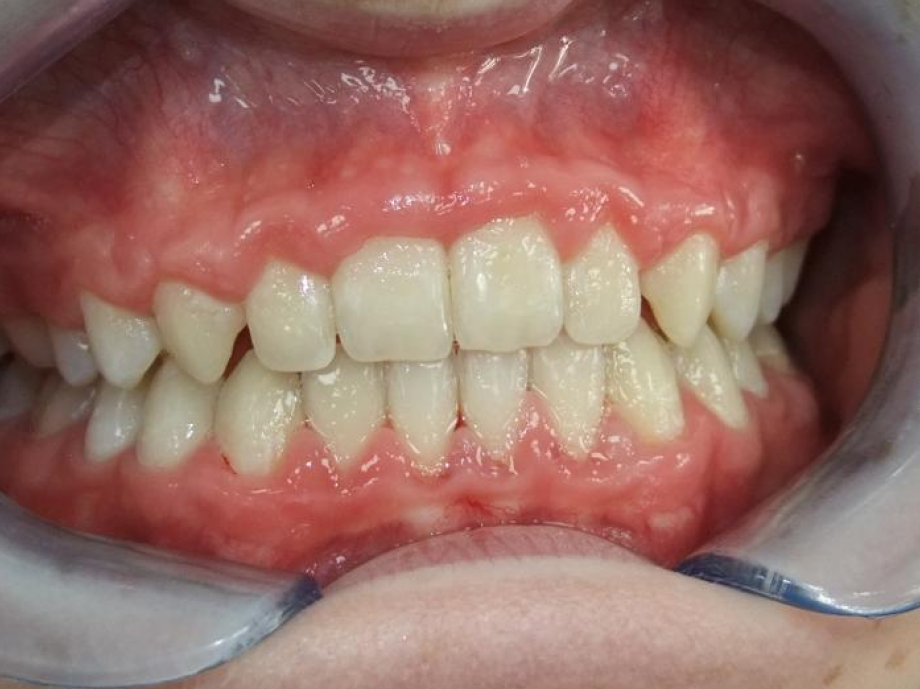

eindfoto

Leeftijd bij aanvang: 9 jaar

1-6 Bonded Hyrax + partieel vast onderkaak + TransForce onderkaak

7-13 Twinblock

13-22 volledig vast onder- en bovenkaak + rotator

Retentie: wrap en c-c bar

Leeftijd bij retentie: 12 jaar